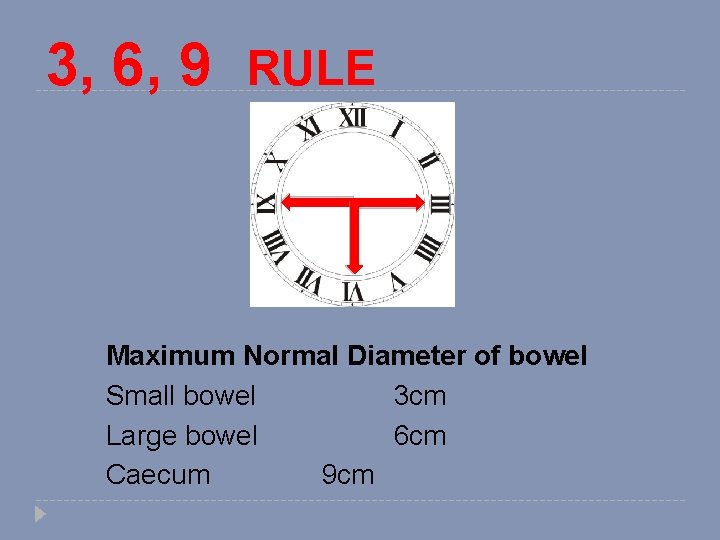

3, 6, 9 RULE Maximum Normal Diameter of bowel Small bowel 3 cm Large bowel 6 cm Caecum 9 cm